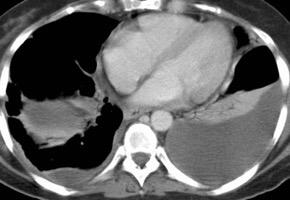

Naidich DP et al. Computed tomography of the diaphragm: peridiaphragmatic fluid localization.J Comput Assist Tomogr1983.

En el corte axial, el líquido pleural se sitúa por detrás